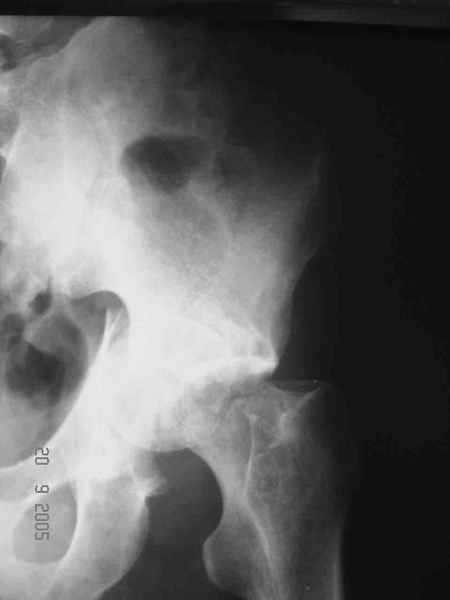

Привет! Вот недавно прооперировали похожий на ваш случай - впадина + шейка (правда у нас впадина поперечный+задний край). После травмы прошло 4 недели. мужчине 46 лет. С такой комбинацией все показания к первичному протезированию. Морально и технически мы к этому уже созрели.Но больной не собрал денег на протез. Выполнили остеосинтез впадины и шейки, прекрасно понимая, что головка вскоре рассосется, мы хотя бы надемся что к этому времени таз срастется, как говорится создали все условия для дальнейшего протезирования (может, и протез в последующем подешевле будет, в смысле, без укрепляющего кольца?). Привет Рункову!